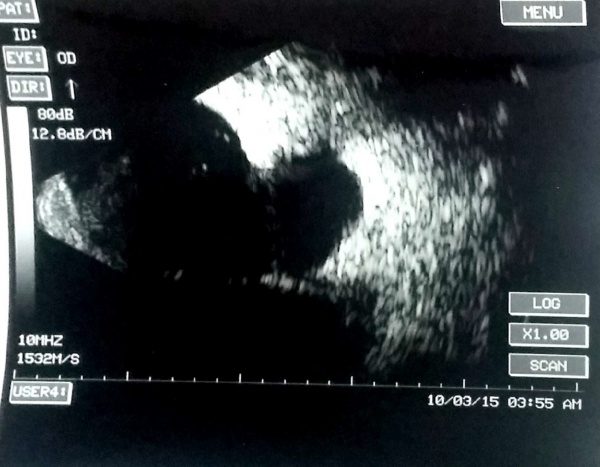

A case of choroidal hemangioma[6] with exudative RD. Note the limited after-movements.